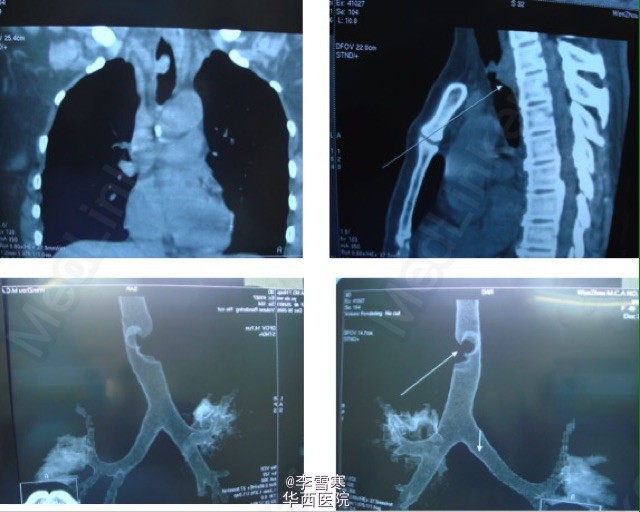

纵隔肿瘤一例,及纵隔肿瘤麻醉的重要原则

纵隔肿瘤

纵隔肿瘤处理的重要原则 1. 如果可能在局麻醉下完成全部操作 2. 尽可能在全麻醉前进行放化化疗 3. 如果必须全麻,应在全麻前进行支纤镜检查和清醒气管插管 4. 如果必须全麻,应保持自主呼吸